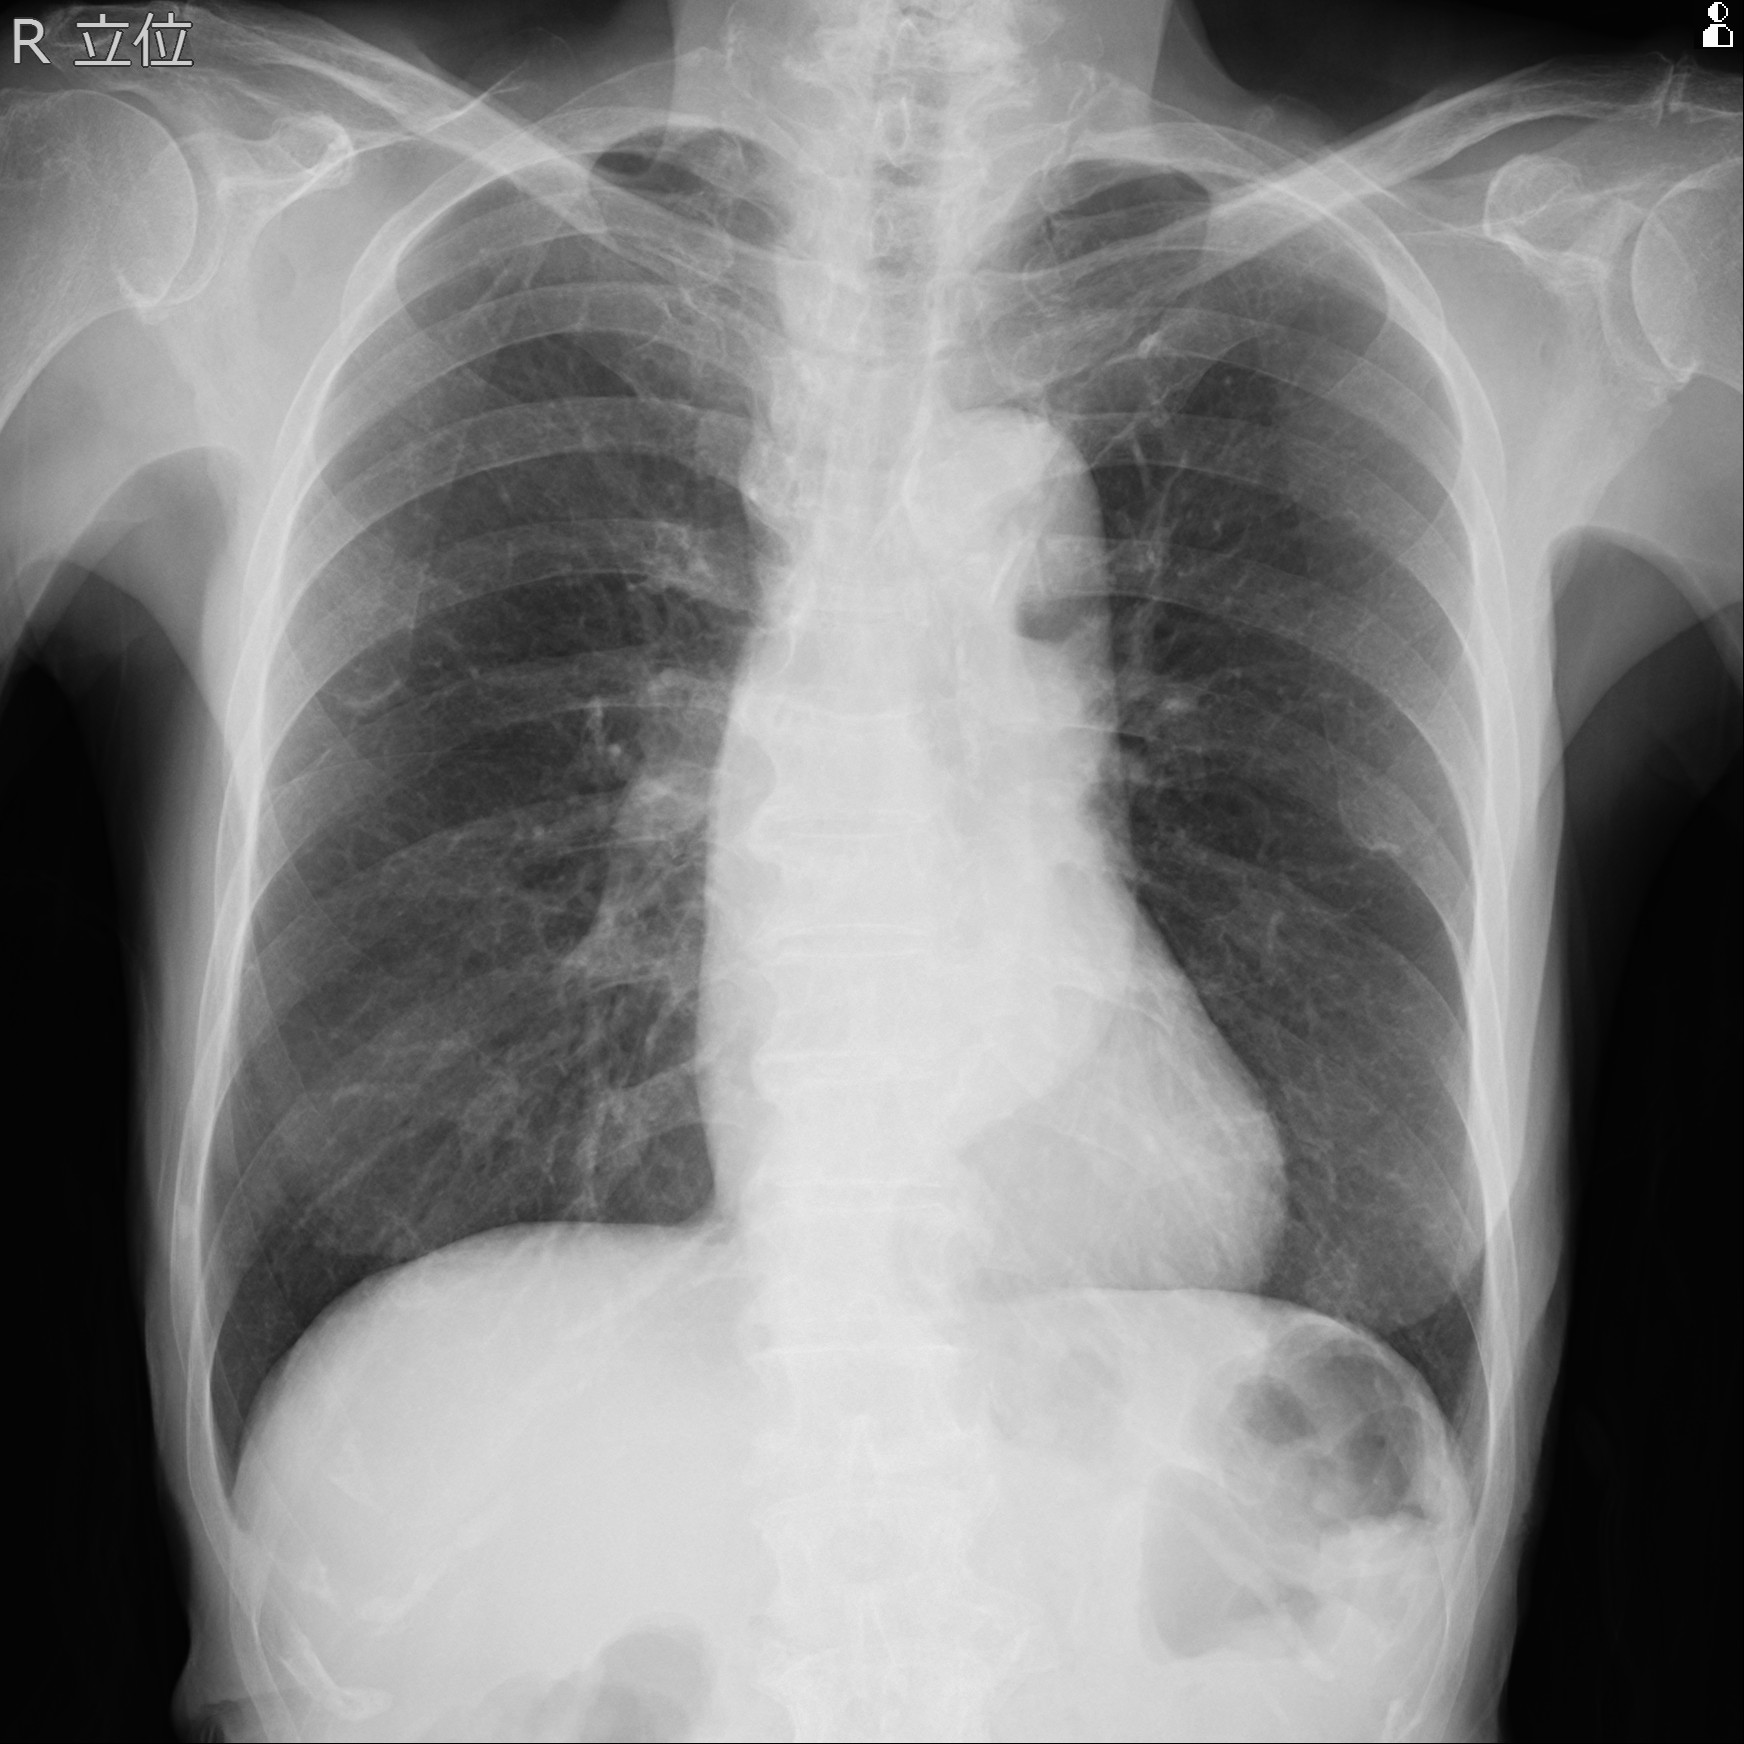

Blood test showed as follows. Renal function was normal (eGFR=63.7), LDL-C was 47mg/dl, HbA1c was 5.3%. ECG showed sinus rhythm and no ST-T change. Chest X-ray showed no pulmonary congestion, and CTR was 49%. Echocardiogram showed no asynergy and normal LV function (EF62%) with mild-moderte AR.